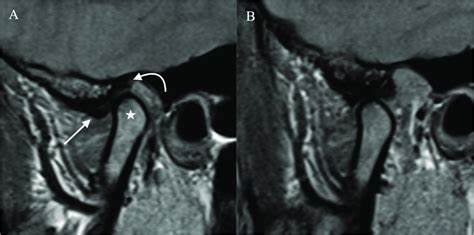

2. Internal Derangement

Clinical Presentation: Jaw pain, locking of the jaw, and limited jaw movement.

Zebris Findings: Abnormal positioning or movement of the condyles, evidence of disc displacement with or without reduction.

Zebris vs. MRI:

- MRI shows soft tissues (including disc position) that Zebris cannot

- Zebris shows dynamic movement that MRI cannot capture

- MRI is more expensive and less accessible

- Ideal approach may include both for complex cases